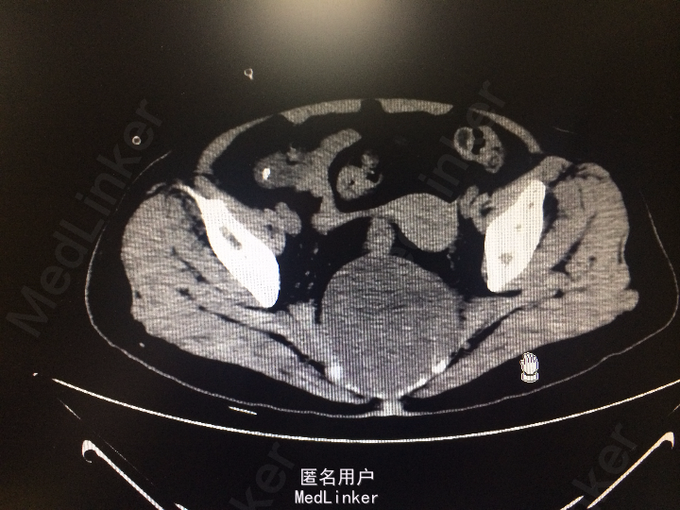

老年女性 主诉:腰背痛半年余,大小便失禁1周。 病史:患者于半年前腰部扭伤后,出现腰痛、腰部无力,需借助外力站立和行走。自诉四肢肌肉力量间断出现减弱,容易出现肌肉僵直,并有肌肉颤动感。半年来,患者多卧床休息,未接受正规治疗。10余天前,出现胸部疼痛,并向背部放射,病人烦躁、易怒,难以入睡、胃纳差、大便次数少。1周前出现大小便失禁,体重近1月下降10余斤。

查体:脊柱生理弯曲存折,腰椎棘突间触痛(-),双侧腰椎旁叩痛(-),活动自如,关节无红肿,双侧下肢肌群肌力正常,双侧下肢外侧皮肤痛、温觉正常,未引出病理性反射,尾骨未触及。 辅查:外院X线:腰骶角增大,提示腰椎失稳可能;腰椎轻度退行变;S3以下骨质结构缺如。

诊断:骶尾部肿物:脊索瘤? 处理:完善各项检查后,为明确具体病理类型行骶尾部肿瘤穿刺活检术,病理明确后行腹腔镜辅助下骶尾部肿瘤切除术。

脊索瘤起源于胚胎残留的脊索组织。50 %的脊索瘤都发生在人体骶尾部。如果肿瘤侵犯脊柱,通常可出现脊髓压迫征,直接浸润,累及腹膜后组织,肿瘤足够大时,可以造成肠腔狭窄,或侵犯膀胱。就骶尾部脊索瘤的治疗方面而言,手术治疗解剖位置深在,手术暴露困难,加之起病隐匿,病程较长,患者来诊时肿瘤已经广泛侵犯周边组织,因此手术难度较大。该病人肿瘤尚完整,除骶骨骨质外未见侵犯其他组织,因此手术切除仍为较好的治疗方法。术后可加用辅助放疗可降低复发率。